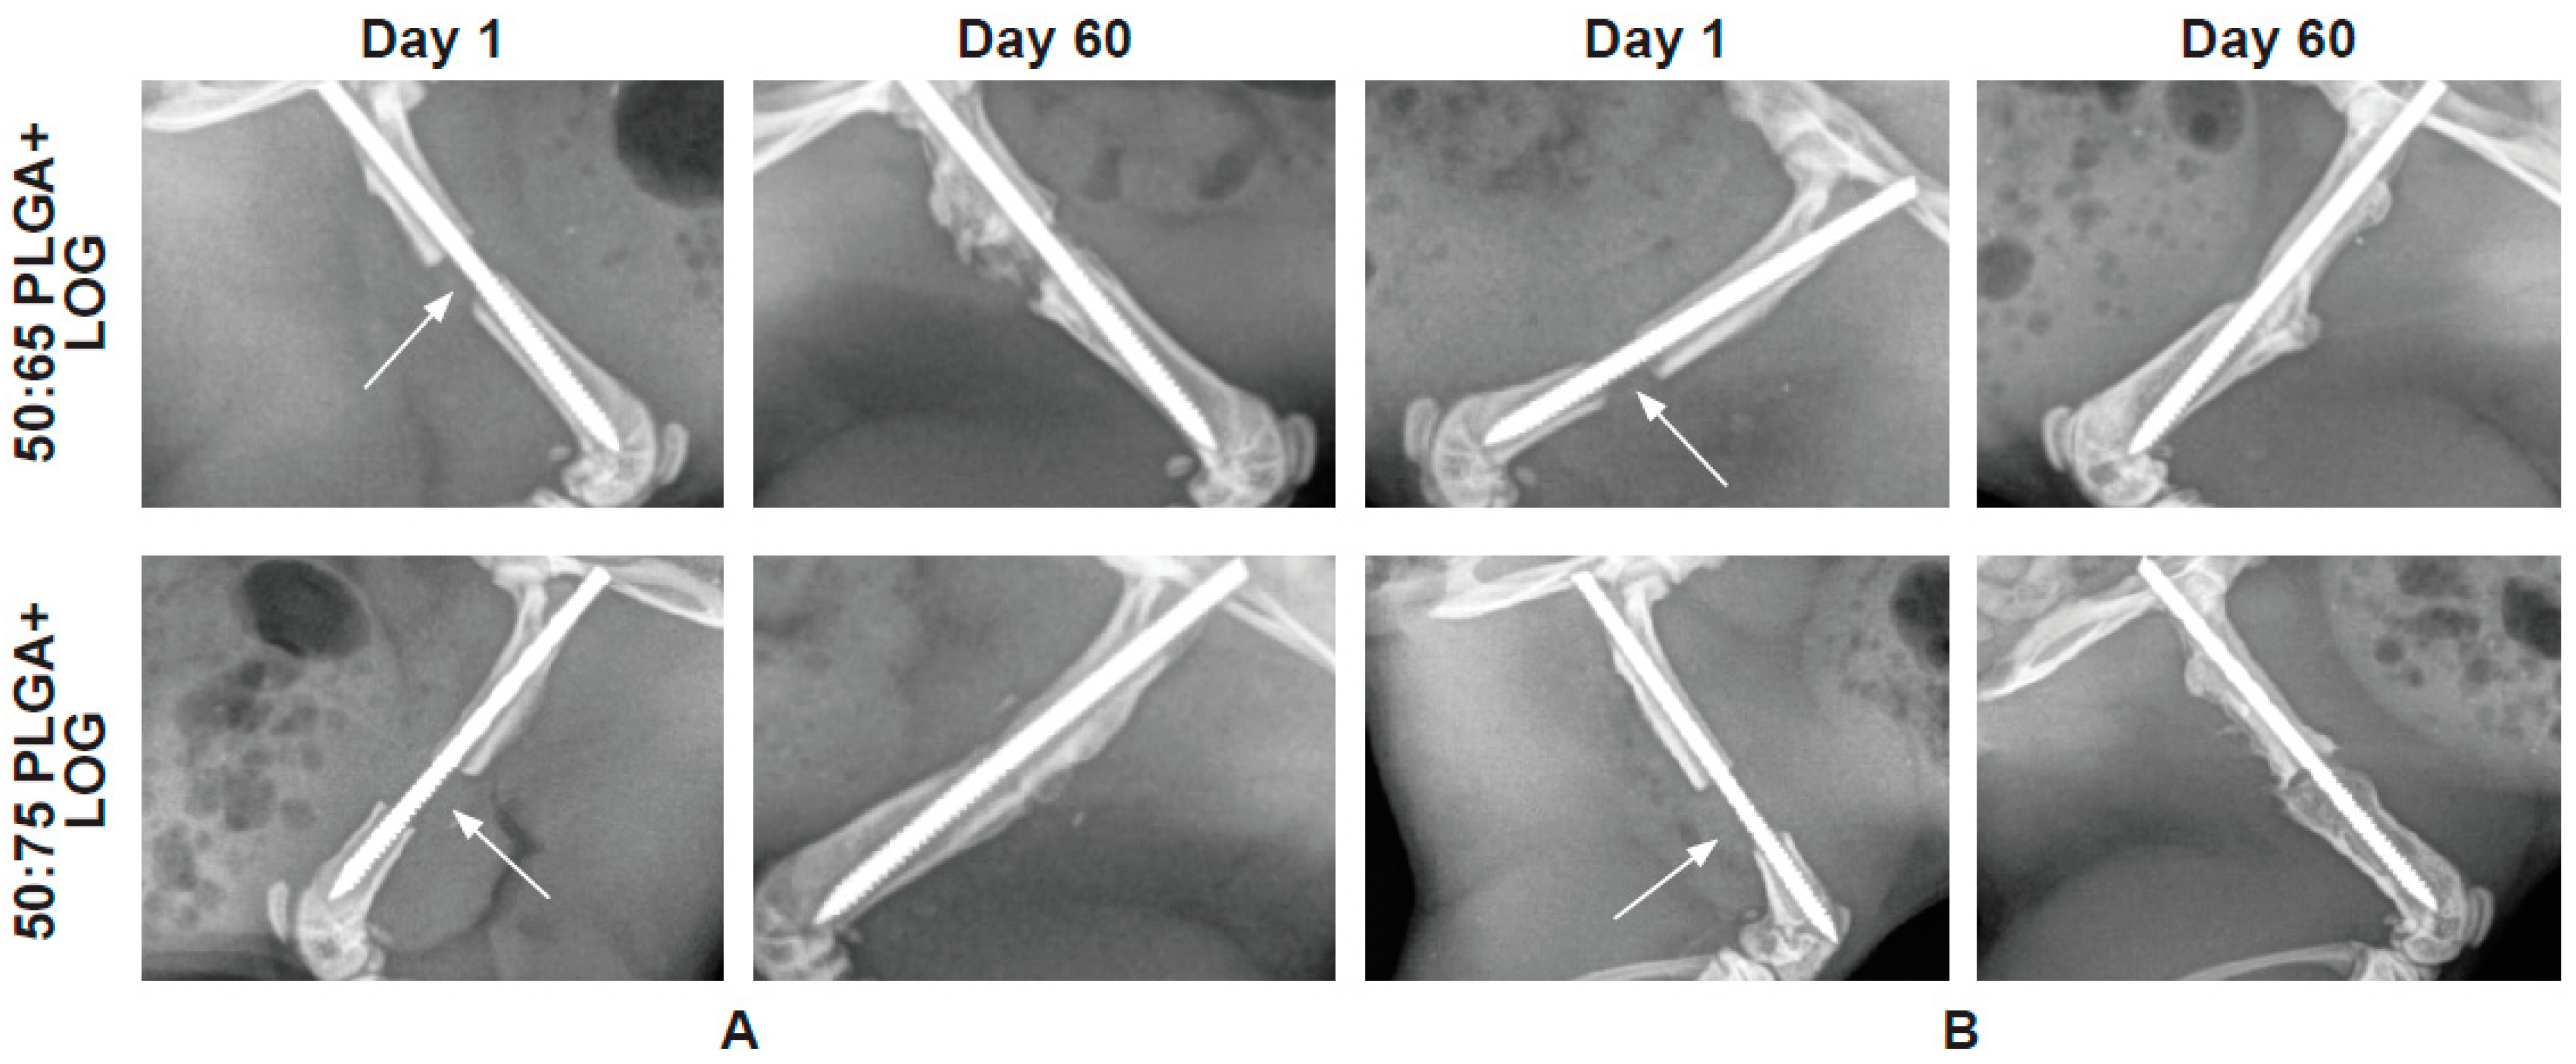

3.4. The PLGA–LOG Scaffold Is Osteoconductive and Osseointegrative